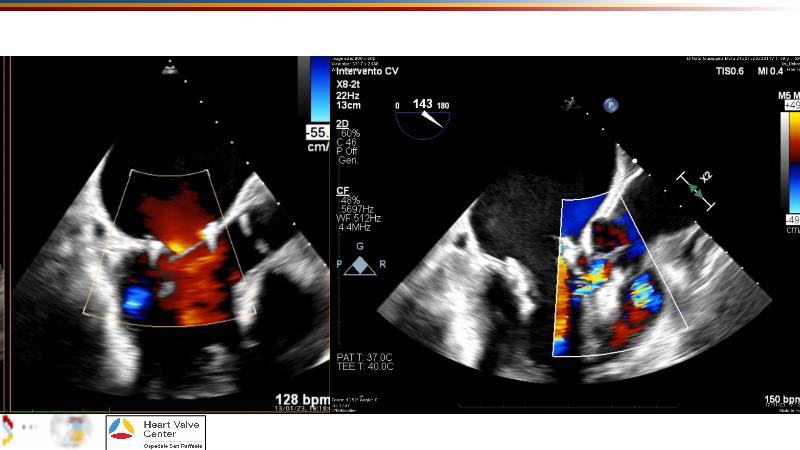

Explore cutting-edge transcatheter valve interventions for mitral and aortic valve disorders, including valve-in-valve procedures and management strategies for paravalvular leakages, and learn about diagnosing and treating mitral annular calcification and transcatheter options in infective endocarditis.

- To get tips and tricks for guidance of transcatheter intervention